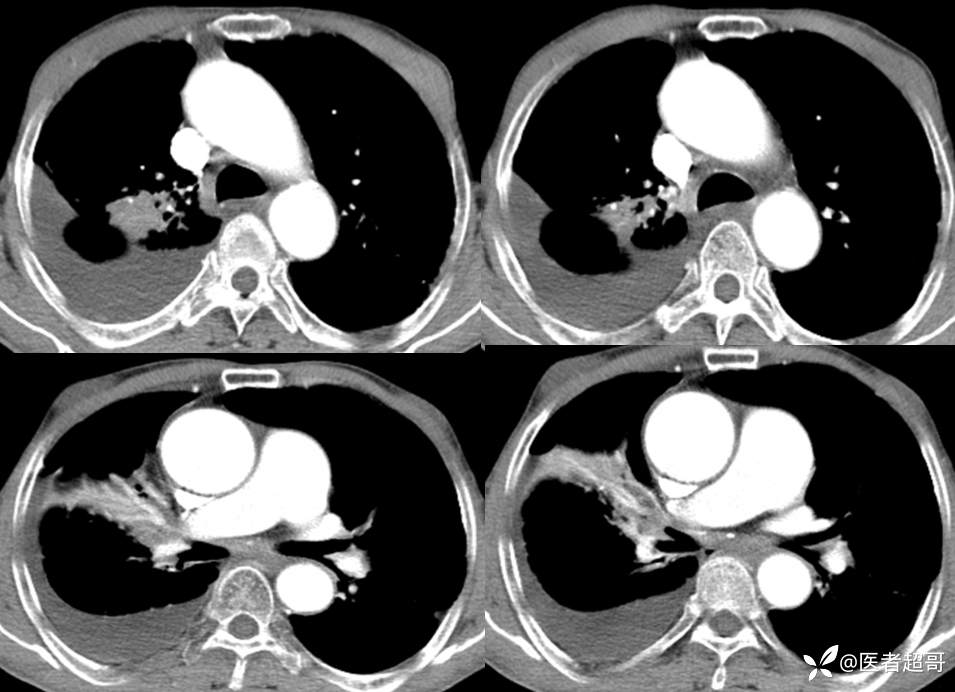

患者,男,72岁,农民,于2021年05月26日17时20分因"发作性精神行为异常10+天"入院。@丁香影像频道

肺炎支原体肺炎 (105)